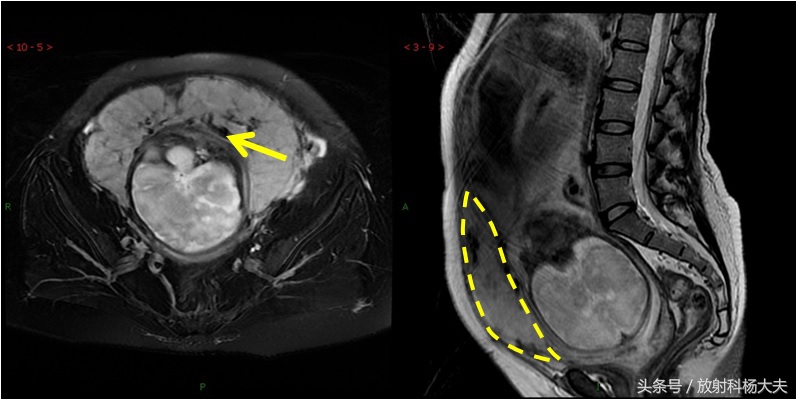

在MRI上显示植入部位子宫肌层局部均不同程度地变薄,胎盘基底面不规则。低信号的子宫肌层内见局部高信号病灶,呈结节状或三角形、锯齿状、不规则形,T2WI胎盘内信号不均匀,内可见较多、粗大的流空血管影和低信号带。严重时胎盘可穿过肌层,穿通部位肌层信号中断,胎盘基底面与子宫壁融合,分界不清。但请注意,目前的技术,MRI的诊断准确率也只能做到82%而已。

胎盘植入的MRI图。黄箭所示黑黑的东西就是一些粗大的血管,能够想象这些血管破裂会有多可怕的后果。另外出血的原因是胎盘植入到子宫壁内,难以剥离。